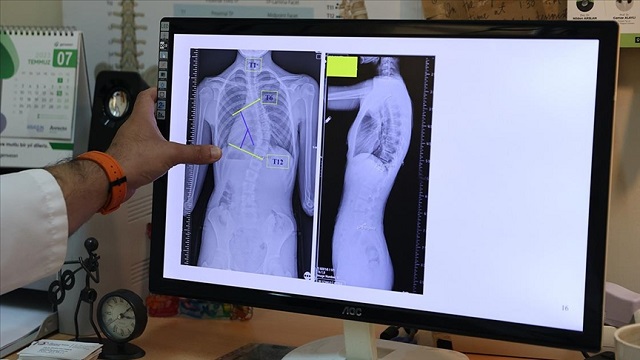

Doç. Dr. Coşkun, omurganın ön ve arka planında 10 dereceden fazla olan eğriliği skolyoz hastalığı olarak kabul ettiklerini belirtti.

Skolyozun duruş bozukluğundan ayırt edilmesi gerektiğini vurgulayan Coşkun, duruş bozukluğunun basit egzersizlerle düzelebileceğini, skolyozda ise omurga yapısında bir deformasyondan söz ettiklerini anlattı.

Coşkun, skolyozun genellikle 10-19 yaş aralığında görüldüğüne işaret ederek, "Skolyoz, nedeni bilinmeyen bir hastalıktır. Ergenlik, adölesan idiopatik skolyozun en sık görülen yaş grubunu oluşturmakta. Şikayetler genelde omuzların bir tarafında yükseklik farkı olması, bir omuzun daha yukarıda yerleşmesi. Ayrıca hasta öne doğru eğildiğinde, hastada bir tarafında sırtında bir yükseklik, bir kamburluk bulgusu olması. Bu yükseltinin bir tarafta belirginleşme, diğer tarafta silinme, skolyozun ana bulgularındandır." dedi.

"Skolyoz hastalığında tedavilerden biri gözlem tedavisidir. Gözlem skolyozda bir tedavidir. Biz gerçekten de 0 ila 20 derece arasındaki eğriliklere pek bir şey yapmayız. Bu çocukların gelişimini takip ederiz ve erişkin yaşa geldiğinde de bu tedaviyi sonlandırırız. Artık bu çocukların bir riski, hastalığın ilerlemesi açısından yoktur. 20 ila 40 derece arasında ise ya da 45 dereceye kadar biz çocuğun yaşı eğer uygunsa korse tedavisi uygularız. Korse tedavisi için çocuğun büyümesinin devam etmesi lazım. Kemik yaşı tamamlan, büyümesi tamamlanmış bir çocukta korse tedavisinin yeri yoktur. 45 dereceyi aşan eğriliklerde ise eğriliğin her sene ilerleyeceğini öngörerek cerrahi tedavi uygulamaktayız."

Skolyozun özellikle kız çocuklarında daha sık görüldüğünün altını çizen Coşkun, ergenlik öncesi çekilecek bir omurga röntgeninin tedavide daha iyi yol alınmasını sağlayacağına işaret ederek, "Kız çocuklarında doğumsal kalça çıkığında olduğu gibi skolyoz yönünden tedbirli olmakta fayda var. Özellikle adet öncesi dönemde kızların en azından bir omurga röntgeninin çekilmesi, yine erkeklerde de ergenlik öncesi dönemde bir kez omurga röntgeninin çekilmesi olası bir skolyoz hastalığının tedavisine erken başlamak adına önemli. Çünkü tedaviye ne kadar erken başlarsak o kadar iyi sonuç alma ihtimalimiz yüksek." ifadelerini kullandı.